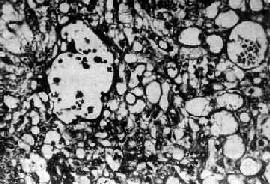

图13-23 内胚窦

呈疏松网状粘液样结构,其中有互相沟通、衬以上皮的腔隙及小囊腔,在细胞内外可见嗜酸性玻璃样小球及基底膜样物